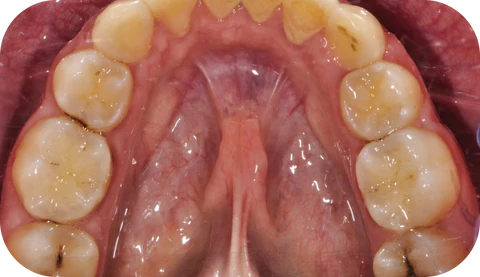

Tooth decay does not start as a hole in your tooth.

It begins much earlier, as a process called demineralization. This is when acids from bacteria start to weaken the enamel, creating tiny areas of damage that are often invisible to the untrained eye.

At this stage, your tooth is not yet a cavity. It is a warning sign.